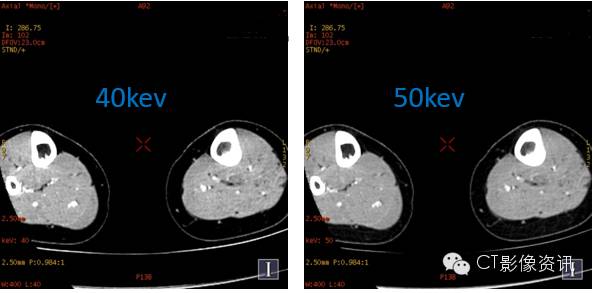

随着单能量水平的减低,左侧胫骨髓腔内的病变显示更加明显;低能量水平图像,可以很好显示小病灶以及轻微的强化病变。 左侧胫骨中段髓腔内转移